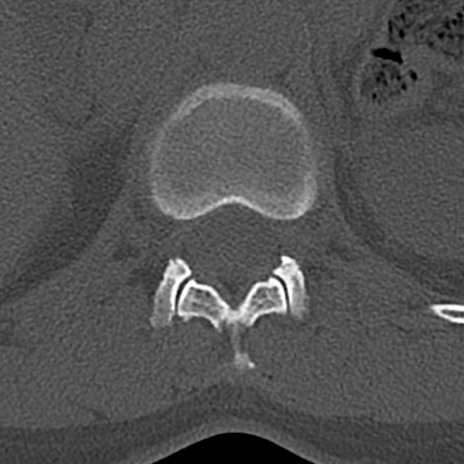

腰椎CT

横断像と矢状断像